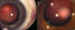

Crioterapia en un retinoblastoma periférico con congelación de la masa

tumoral.

mismo tiempo.  – Alta recurrencia de los focos vítreos y siembras subretinianas.  – Las técnicas focales no solucionan todos los casos (10,11).    Crioterapia  Técnica de elección para tumores pequeños periféricos. Se aplica bajo

control con oftalmoscopio indirecto y a ser posible con un criodo de

descongelación automática (24,25), realizando la triple congelación del tumor

con intervalos de 1 minuto.  Las mejores respuestas se dan con tumores menores de 1,5 mm; entre 1,5-3 mm

el resultado también es muy bueno. Los tumores de 3-6 mm pueden recurrir.  Es el tratamiento de consolidación más utilizado en nuestra serie,

consiguiendo generalmente un patrón de regresión tipo 4. Un método

alternativo es la termoterapia con láser de diodo transescleral.    Termoterapia con láser diodo